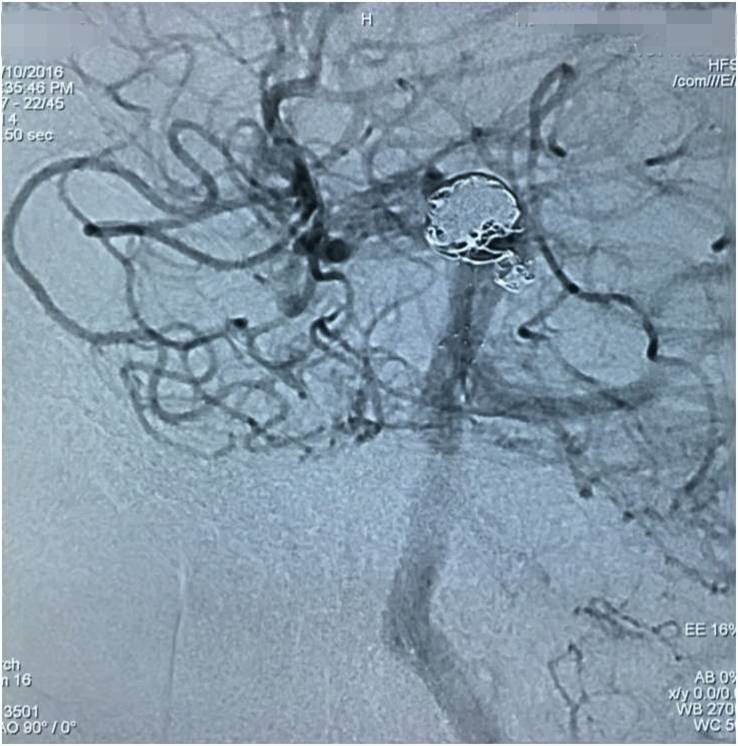

以下图像为DSA,显示基底动脉顶端动脉瘤,左侧小脑上动脉瘤,左侧PCA P1段微小动脉瘤,双侧颈内动脉眼动脉以远闭塞,前循环靠后循环通过后交通动脉代偿。

▼左椎动脉造影正位

▼左椎动脉造影侧位

▼左椎动脉造影三维重建,这个角度可以窥清基底动脉顶端动脉瘤和左小脑上动脉瘤,可见基底动脉顶端动脉瘤顶端的子瘤,考虑是SAH的责任动脉瘤。

▼这个角度可以看到左PCA P1段的微小动脉瘤